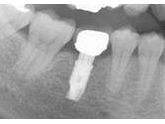

右下の奥歯の欠損をインプラントで修復しました。

両隣の歯は、全くの健全歯でインプラント治療によりダメージなく治療を終えることができました。

|

インプラント埋入状態 |

治療完了状態 |

レントゲン写真 |